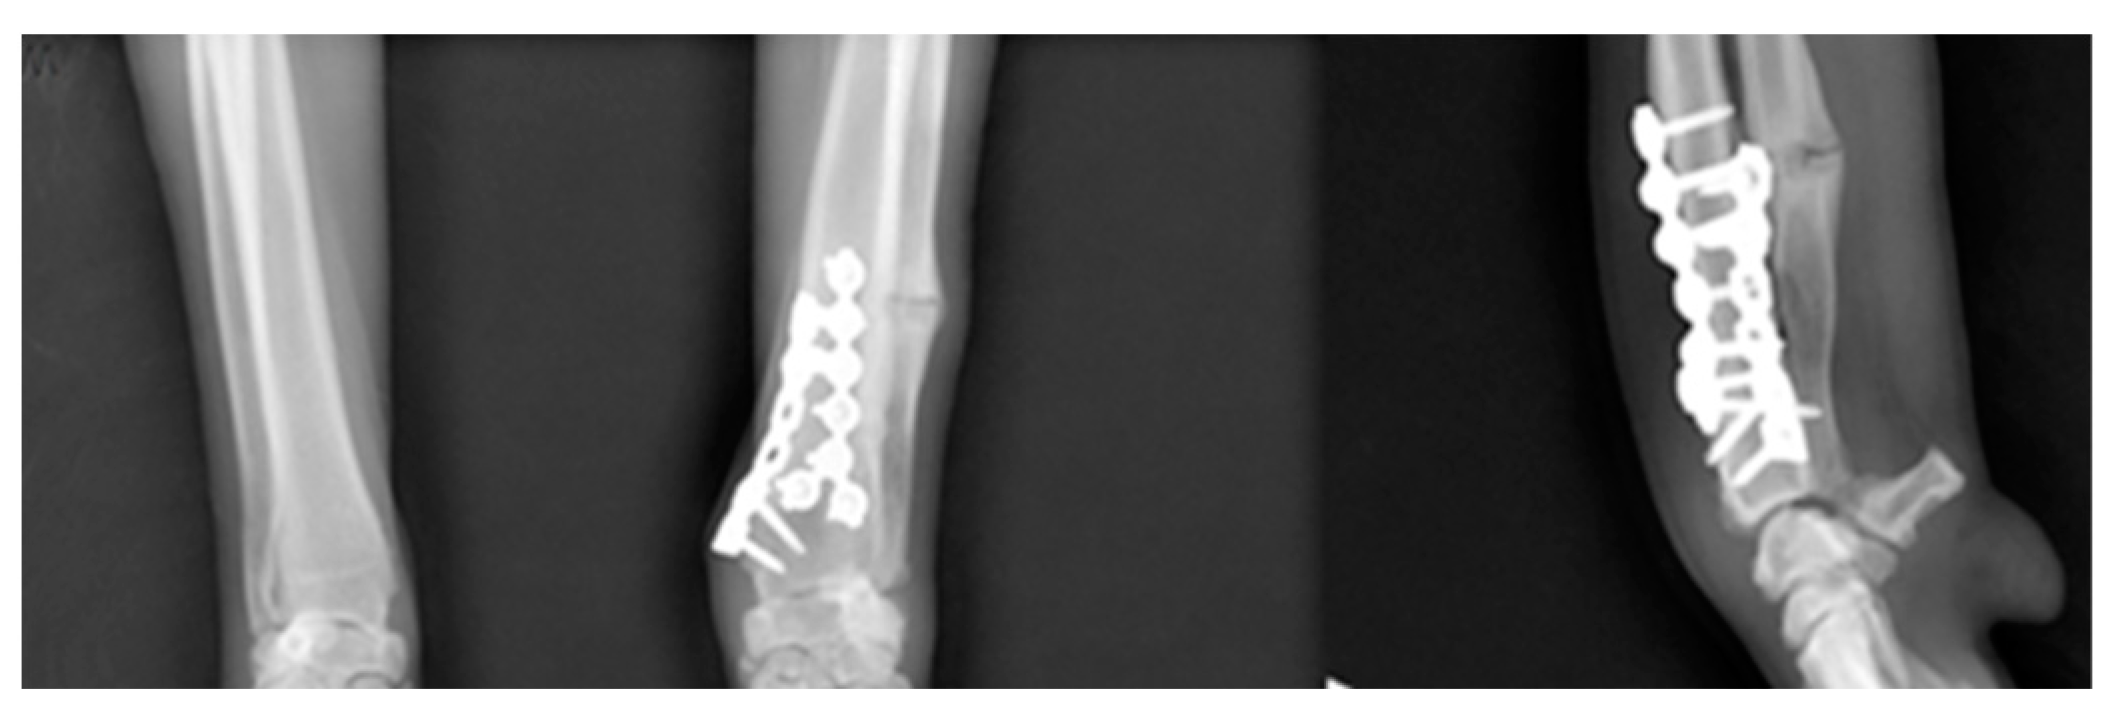

2.5. Surgery and Evaluation

3. Results